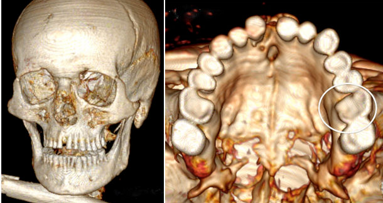

Het 3D-model kan op basis van CBCT-scans 3D-modellen van de kaken, tanden, de schedel, de sinussen en de kaakzenuwen maken. Die verschillende modellen worden dan samengevoegd tot een geheel, een soort ‘virtuele patiënt’. Dit proces duurt enkele seconden.

Het model wordt in eerste instantie aangeboden aan kaakchirurgen, maar kan later ook ingezet worden in de orthodontie. Er zijn ook plannen om toepassingen te ontwikkelen in andere tandheelkundige domeinen zoals in de implantologie.